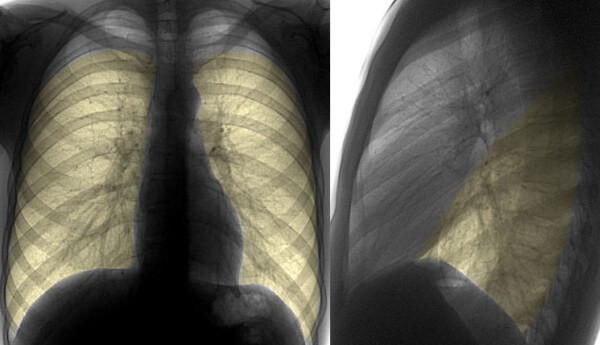

Окончательный диагноз пневмонии устанавливается и подтверждается только врачом согласно результатам анализов и рентгенографии (последняя – самая информативная). Выявить пневмонию, особенно у маленьких детей непросто.

Повышение содержания лейкоцитов и увеличение СОЭ в общем анализе крови и очаги изменений в легочной ткани на снимке говорят в пользу пневмонии.

По форме поражения (выявляется на рентгеновском снимке) пневмония бывает:

- Очаговой (одно- или двухсторонней) – на легком обнаруживаются инфильтративные очаги до 1 см в диаметре. При слиянии нескольких очагов – носит очагово-сливной характер.

- Сегментарной – воспаление полностью всего сегмента с образованием спадения альвеол (ателектаза). При отсутствии эффекта от консервативного лечения может потребоваться хирургическое удаление пораженного ателектазами участка.

Сегментарная пневмония на снимке

- Крупозной – воспаление захватывает полностью всю долю с вовлечением бронхов и плевры.

- Интерстициальной – когда инфильтрат скапливается не только в альвеолах, но в пространстве между ними.